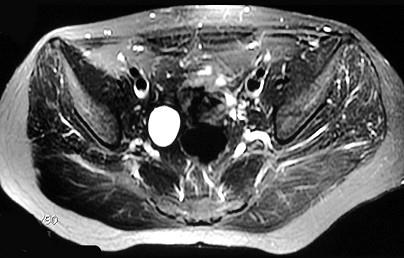

问题 女,31岁,右侧腰部胀痛不适,MRI检查如图所示,下列说法正确的是 ( )

选项 A、左肾输尿管未见异常 B、考虑为右侧输尿管囊肿 C、右侧输尿管粗细不均并迂曲扩张 D、右侧输尿管下段呈囊样扩张 E、右肾重度积水

答案 ABCDE